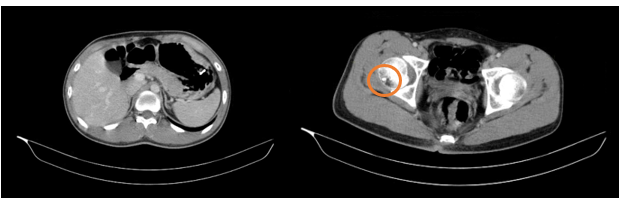

– Cắt lớp vi tính ổ bụng (22/10/2025): Nhu mô gan rải rác các nốt ngấm thuốc mạnh sau tiêm đường kính 6mm. Các nốt ngấm thuốc kém nhu mô lách đường kính lớn nhất 25mm. Các ổ khuyết xương lan tỏa xương cột sống và cánh chậu hai bên – theo dõi tổn thương thứ phát. Dày, tăng ngấm thuốc phúc mạc vùng tiểu khung

Hình 6. Hình ảnh nốt ngấm thuốc kém ở lách (vòng tròn màu cam). Các ổ khuyết xương lan tỏa nhiều vị trí (mũi tên màu xanh) trên phim chụp cắt lớp vi tính.